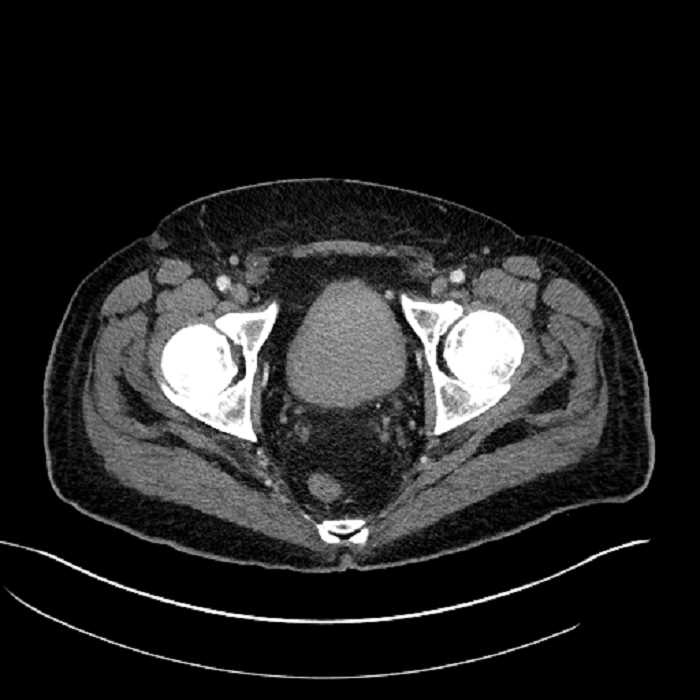

• High grade stenosis of the left common iliac artery, with the left internal and external iliac arteries remaining patent

High grade stenosis of the left common iliac artery. The left external and internal iliac arteries are patent.